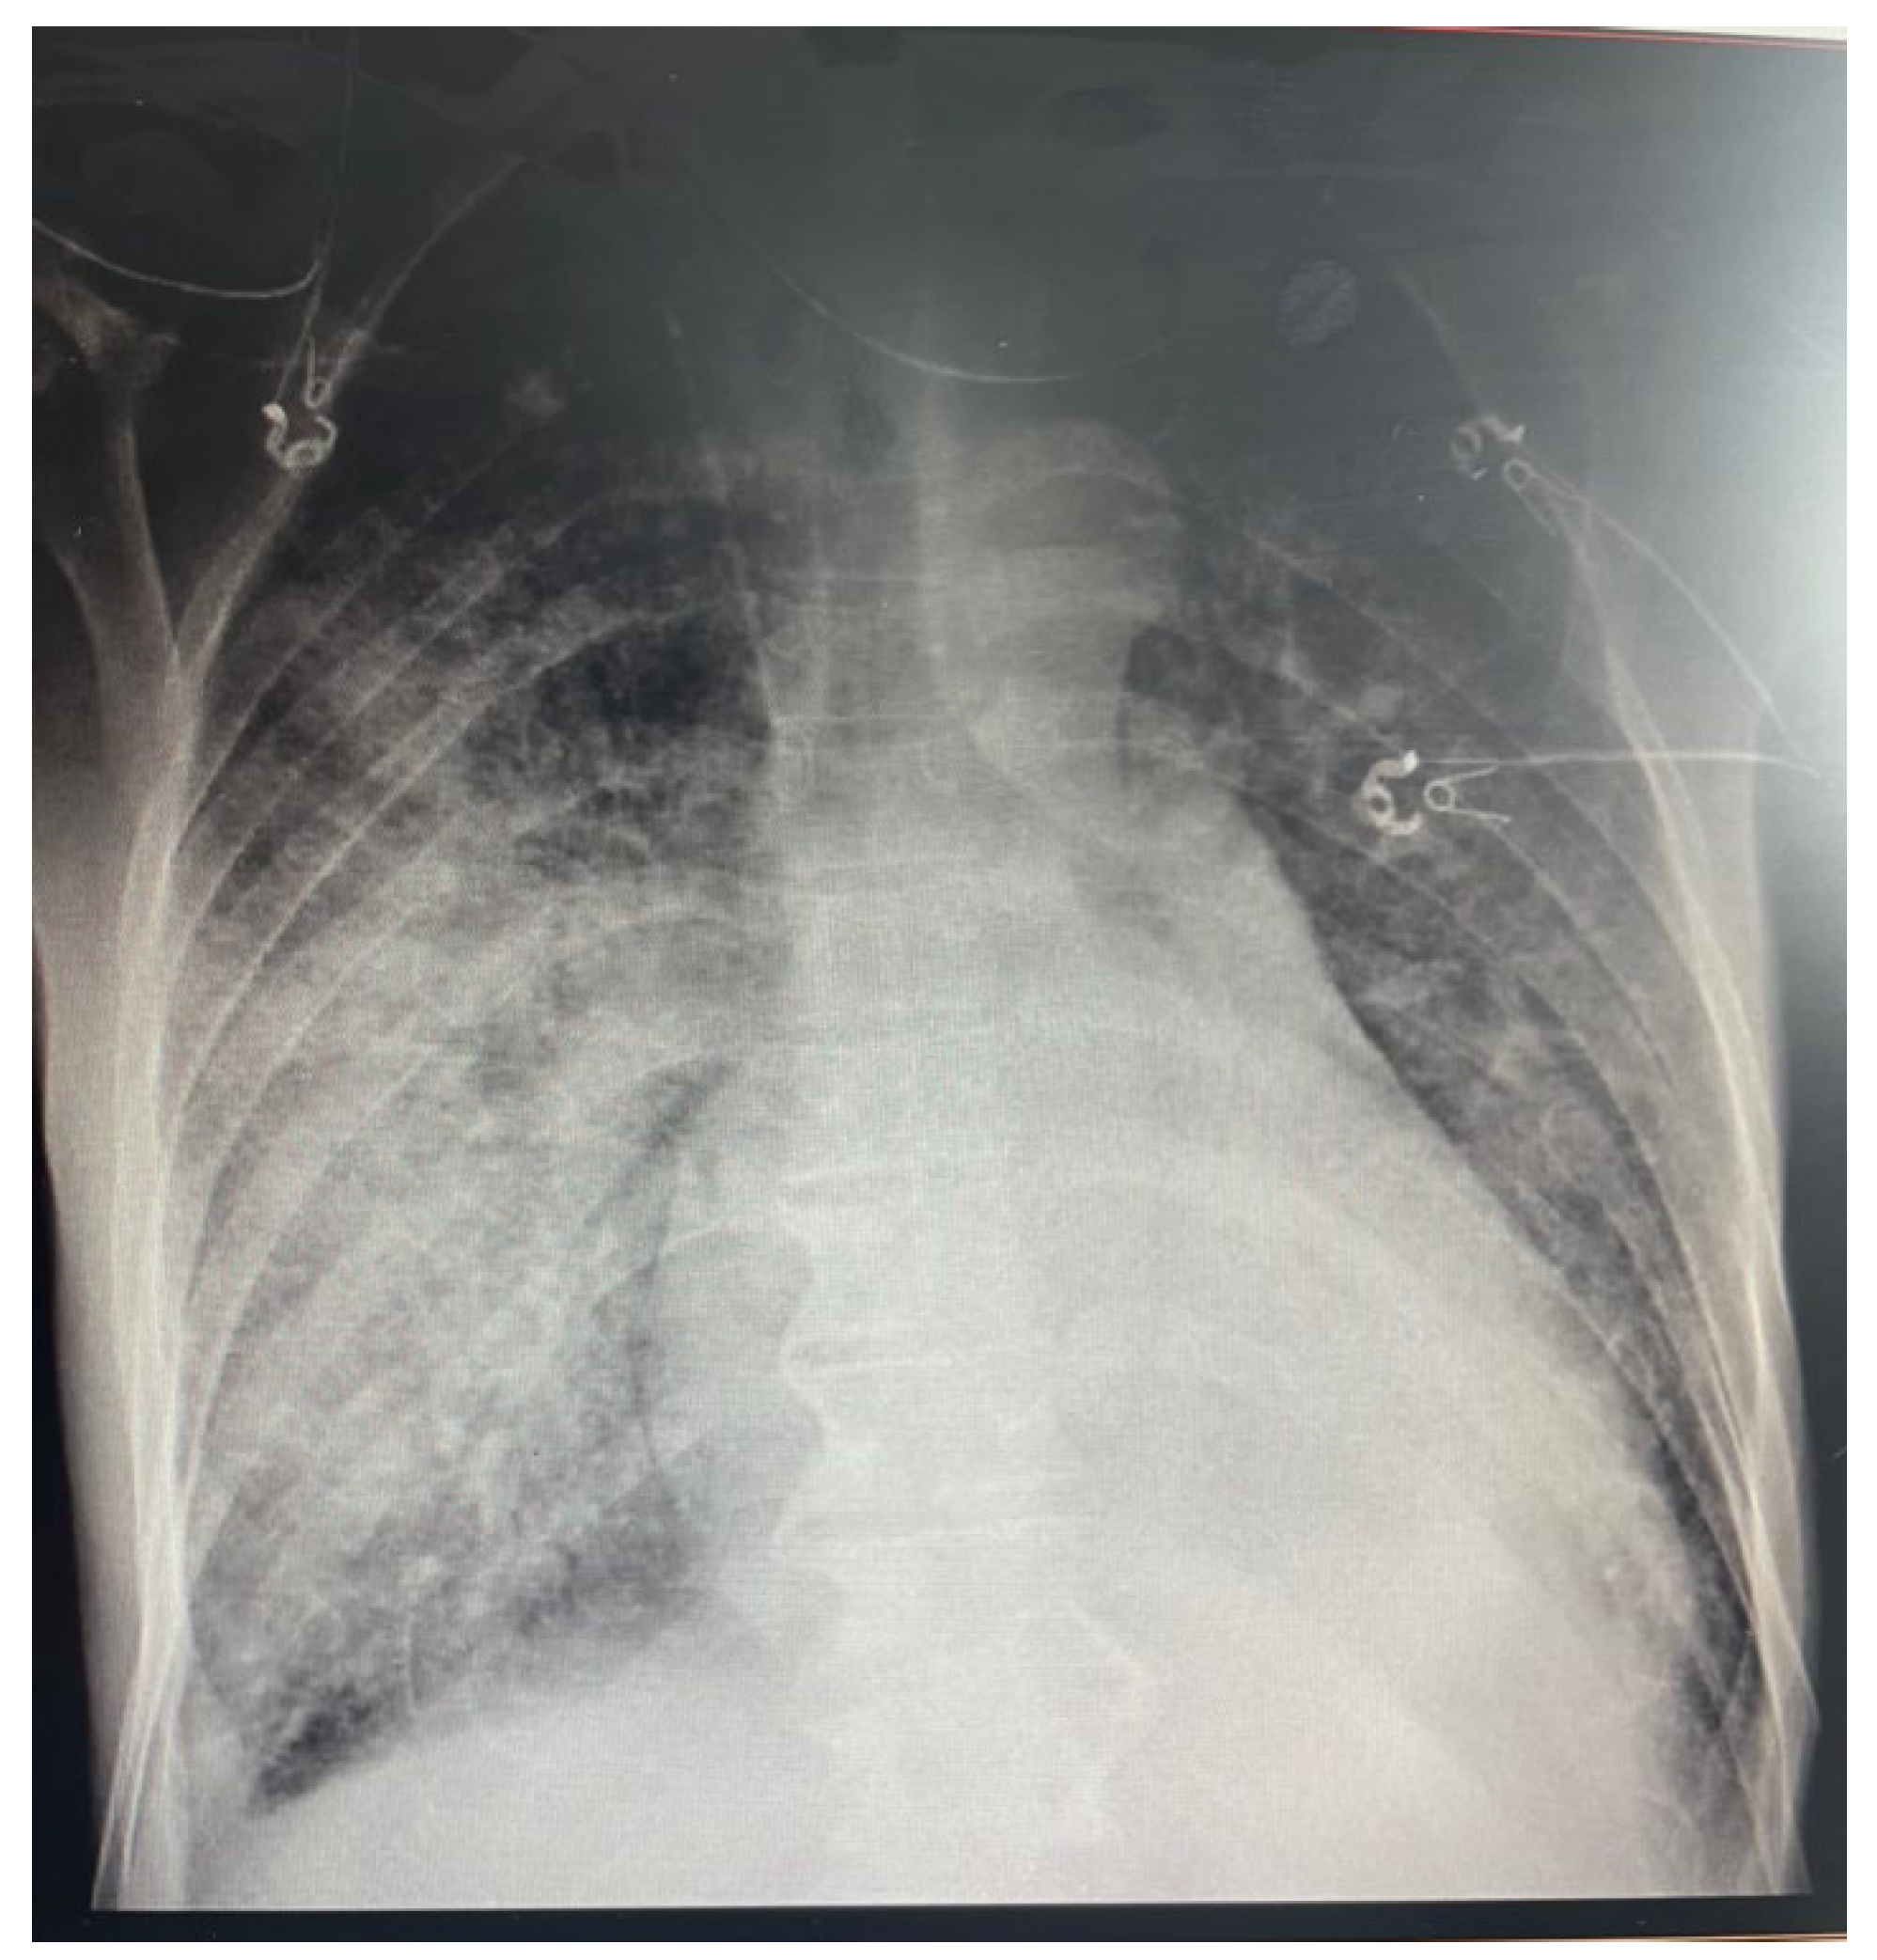

2. Case Report